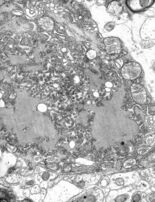

Buruli ulcer is caused by the bacterium Mycobacterium ulcerans.[37] It is related to the family of organisms that cause tuberculosis and leprosy, but Mycobacterium ulcerans produces a toxin, mycolactone, that destroys tissue.[37] The prevalence of Buruli ulcer is unknown.[18] The risk of mortality is low, although secondary infections can be lethal.[38] Morbidity takes the form of deformity, disability, and skin lesions, which can be prevented through early treatment and treated with antibiotics and surgery.[38] It is found in Africa, Asia, and Latin America.[39]